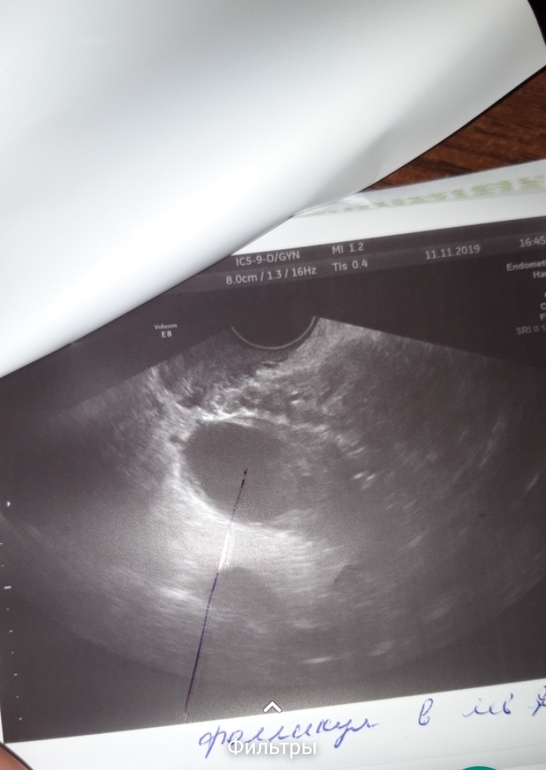

Врач увидела вот это образование,размером 25,не знает она что это,фолликул или жт,в позадиматочном пространстве не значительное количество жидкости,эндометрий 13,а правый яичник она норм и не увидела,а правая сторона нормально так тянет,в общем кто разбирается,это фолликул или же жт? И бывает ли кровоток у доминантного фолликула?

На последнем снимке фоликул. Желтое тело имеет другую структуру. И при фоликуле часто бывает жидкость в позадиматочном пространстве, в маленьком совсем количестве. Когда фолик лопается, там уже жидкости много